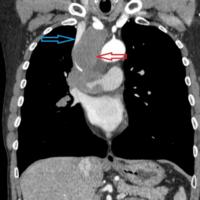

Increased investment in specialist thoracic surgical expertise can lead to a significant rise in the lung cancer resection rate, based on data from England...